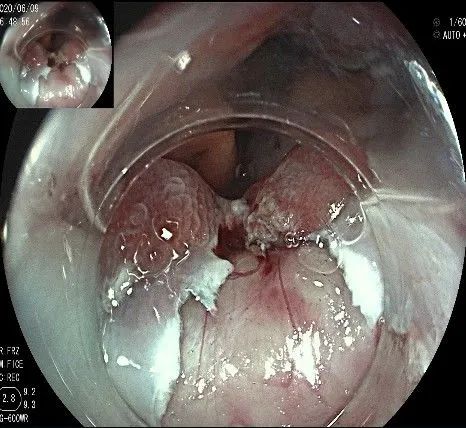

随着剥离的进行,瘤体与周围组织的关系越来越清晰。

此时瘤体基底部已暴露出来,起源于固有肌层。

这是最后的“根”部。

换用IT刀可以轻松剥离,又避免切入过深造成穿孔。

剥离接近完成,最后连接的薄层组织。